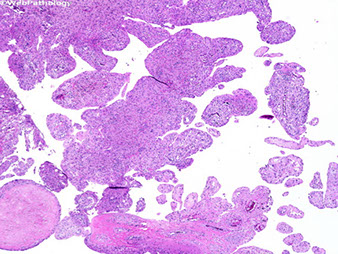

Chondroblastoma

Rare (1/50 bone tumors) cartilage-forming tumor in the proximal (epiphyseal) humerus and distal femur of young pts (<20 yo; skeleton still immature); 2-3M>1F

Micro: sheets of immature reniform chondroblasts dispersed in an irregularly distributed group of osteoclast-like GCs

- look for foci of chondroid matrix and pericellular network of "chicken-wire" calcifications

- commonly see secondary aneurysmal change (up to 1/3 c ABC component)

- different from GC tumor b/c GCs in GC tumor are more evenly spaced

IHC: S100 (+) (same as giant cell tumor), H3F3A +

Tx: curretage

Px: generally excellent; ~1/5 recur, can have "b9" mets to soft tissue and lung

- mets should raise suspicions on initial dx; should review original dx to make sure it was chondroblastoma

Chondroblastoma - chicken wire calcs

Do not be fooled by the giant cells!!